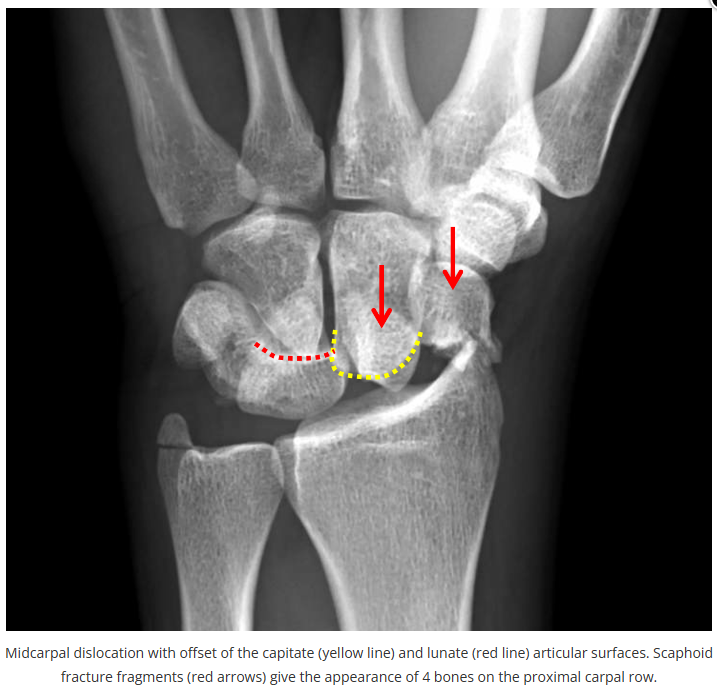

今天是腕部与手的X线片。所有X线片都

带有标注和说明

,可以选择长按图片,

自动翻译相关说明